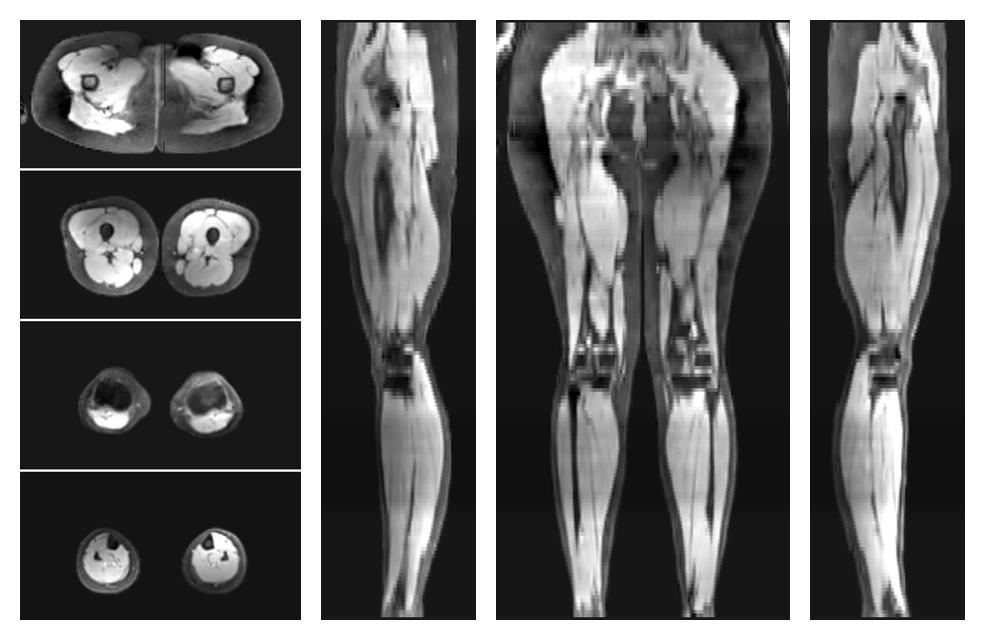

• Water only signal

The water part of the acquired multi-echo spin echo data.